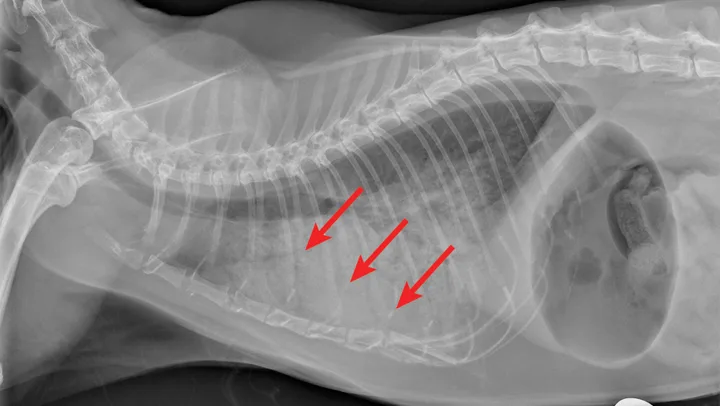

Thoracic radiographs may reveal a bronchointerstitial pattern, alveolar infiltrates, a diffuse bronchial pattern, and (rarely) pleural effusion (Figure 5).10,11 Diagnosis may be made via identification of first-stage larvae from airway cytology specimens or fecal samples. In clinical practice, false-negative fecal samples have been appreciated due to intermittent fecal shedding. Repeated testing may increase sensitivity but has not been evaluated. Therefore, any patient suspected of potential lungworm should be treated. Less common lungworms have been reported in cats, including Paragonimus spp12-14 and Capillaria spp.15

FIGURE 5A

Radiograph of aelurostrongylus abstrusus infection (lungworm). Note the diffuse bronchial pattern (orange arrows), patchy poorly defined soft-tissue nodules (red arrows), and right middle lung lobe alveolar disease (yellow arrow). This pattern could be confused with feline asthma in this case; however, the right middle lung does not appear atelectatic but instead infiltrated. Fine-needle aspiration of the right middle lung lobe confirmed larvae.